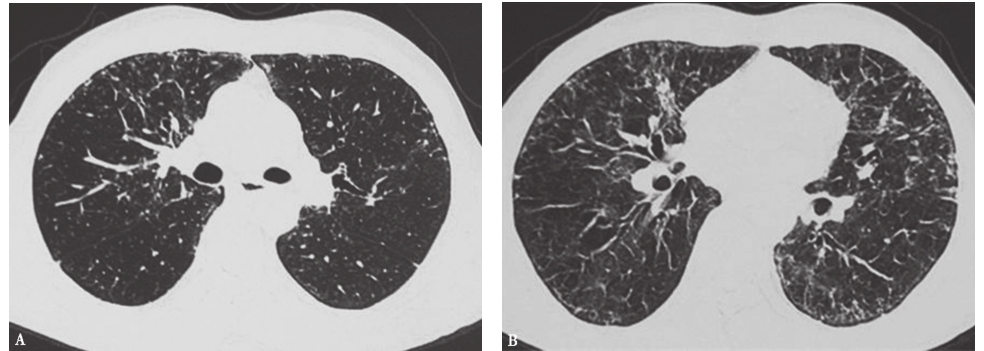

患者经泼尼松(20mg,每天2次)口服治疗,并且脱离原有工作环境,1个月后复查胸部HRCT示两肺磨玻璃影及小结节影较前进一步吸收(图17),咳嗽、气喘症状明显缓解。

图17泼尼松治疗1个月后胸部HRCT表现-6902304544819200

图17泼尼松治疗1个月后胸部HRCT表现

HRCT显示磨玻璃影及小结节影进一步减少,双肺胸膜下少量小结节影